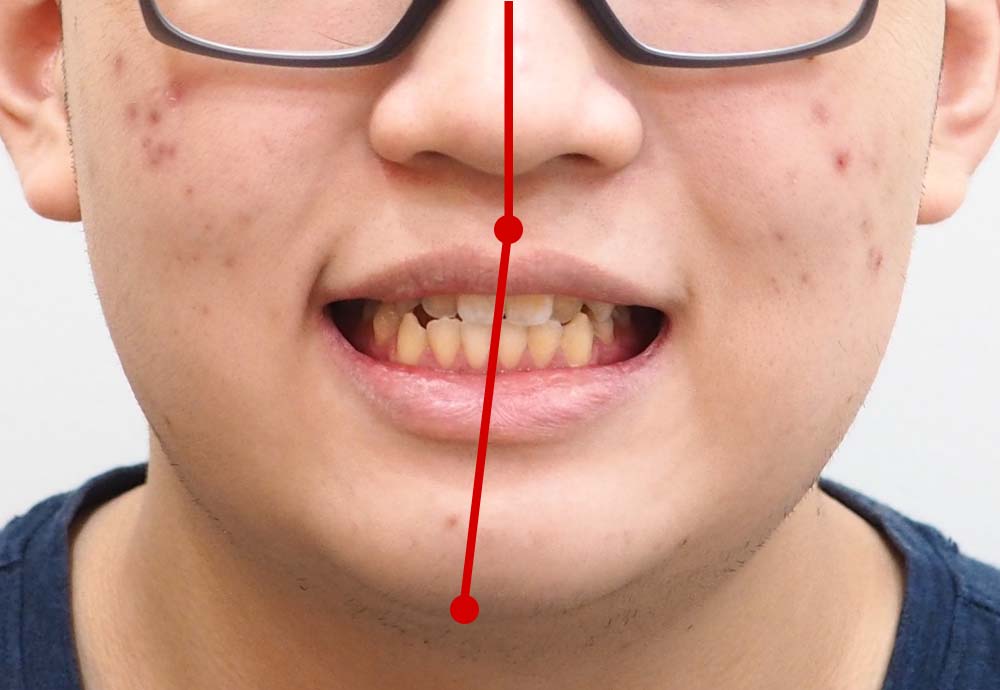

Dental Condition: Protruded side profile

Not guided just by a feeling, but an artistic process guided by scientific measurements.

Unlike metal braces that often rely on extraction to create space, clear aligners allow gentle arch expansion and digitally planned movement (distalization etc) to ensure the least compromise in facial profile.

Perfect if your facial profile makes you unsuitable for extraction.